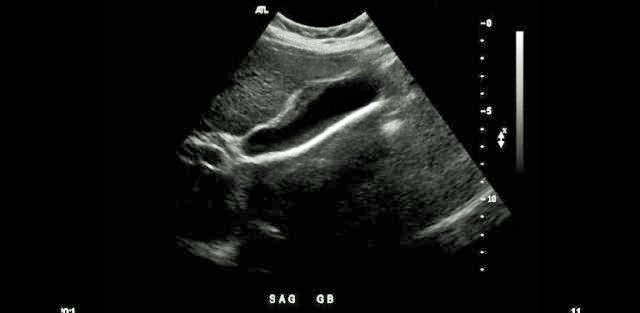

Which of the following statements is true regarding the image displayed?

The gallbladder has a normal variant called a Phrygian cap near the fundal area

Which portions of the gallbladder and/or Billary tree are involved in the formation of a Phrygian cap?

Body and Fundus